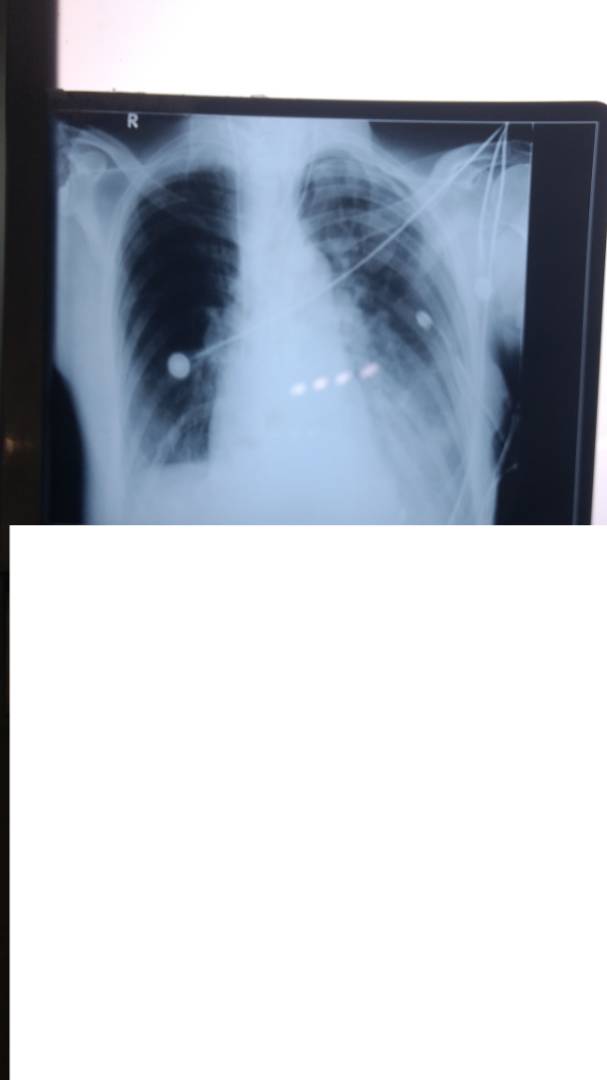

X rays